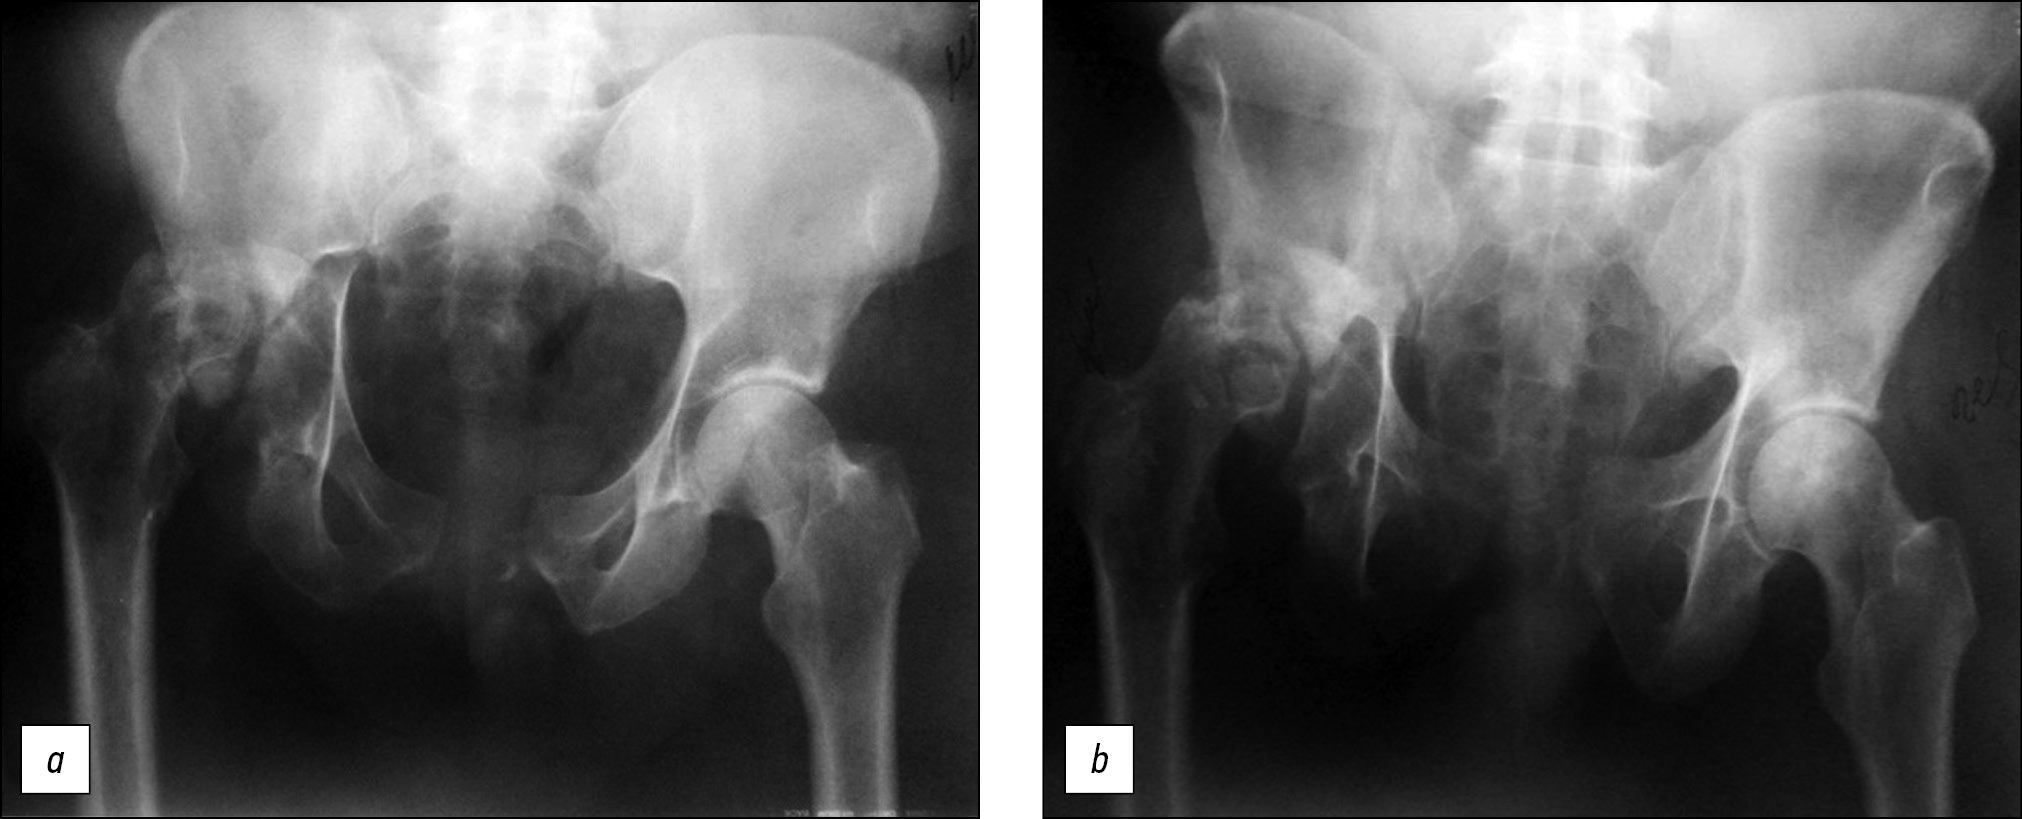

Клинический пример № 1. Пациент, 52 года, травма в результате дорожно-транспортного происшествия 1 год 1 мес назад. По месту травмы проводилось консервативное лечение со скелетным вытяжением за бугристость правой большеберцовой кости в течение 1 мес. Пациент поступил в первое отделение ФГБУ НМИЦ ТО им. Н.Н Приорова спустя год после травмы с диагнозом: «Застарелый разрыв лонного сочленения. Неправильно срастающийся перелом правой вертлужной впадины. Асептический некроз головки правой бедренной кости. Застарелый вывих головки правой бедренной кости. Разрыв правого и левого крестцово-подвздошного со-членения» (рис. 1).

Рис. 1. Пациент, 52 года. Рентген через 1 год после травмы: а — прямая проекция, b — краниальная проекция

Fig. 1. Patient, 58 years old. X-rays 1 year after injury: a — frontal, b — out-let